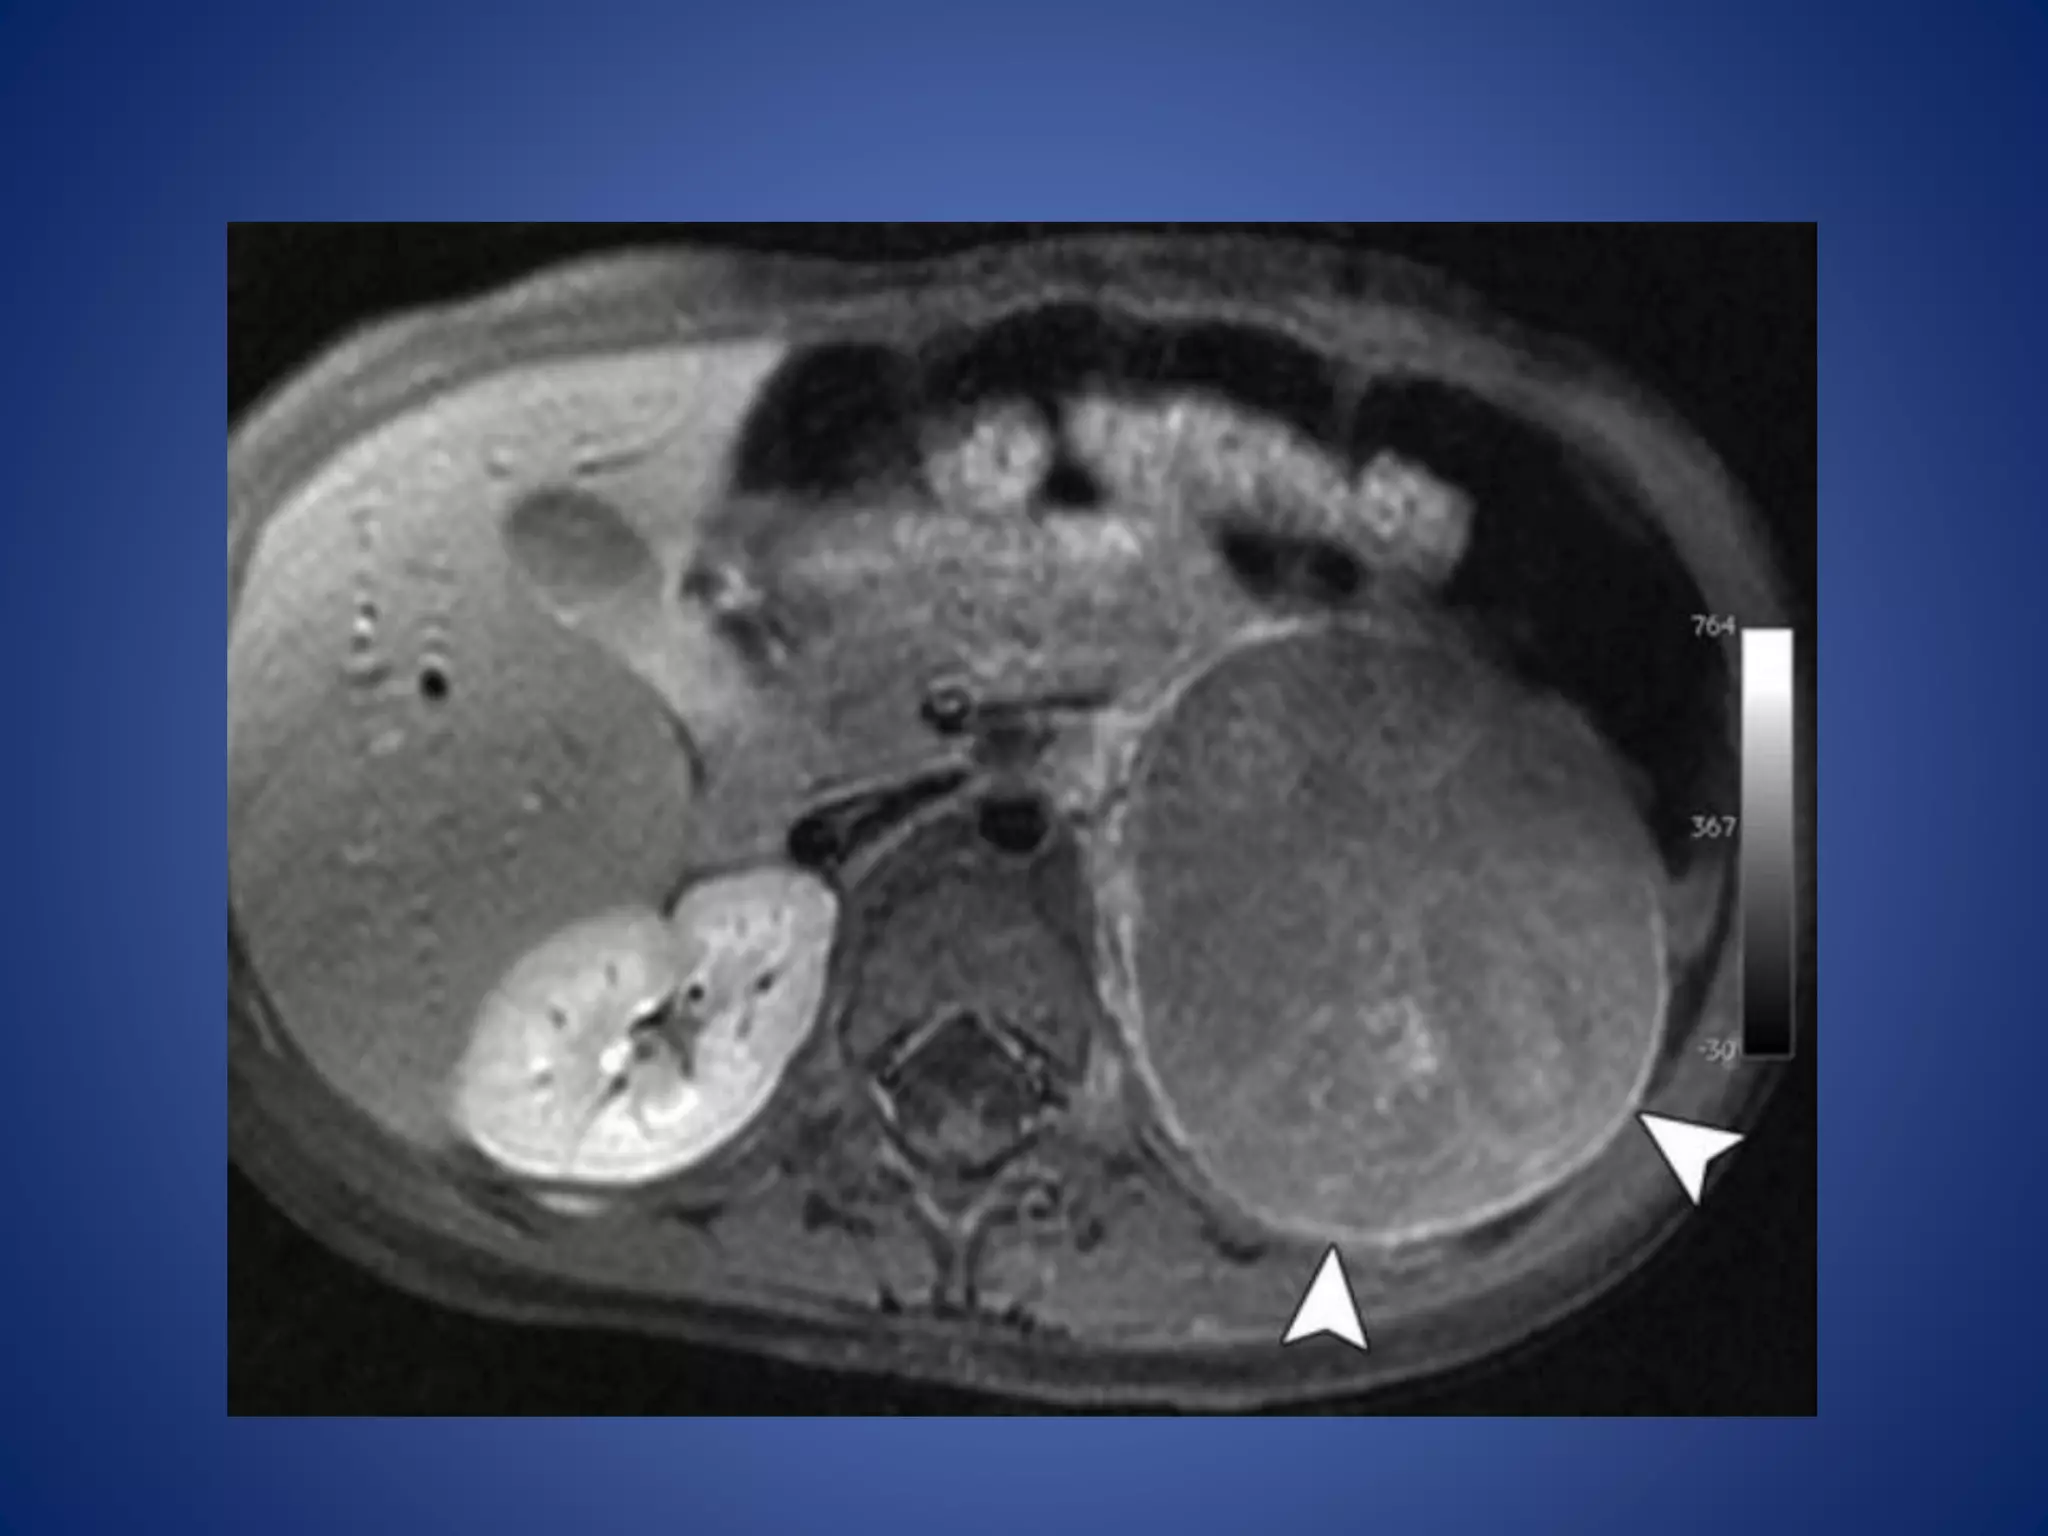

MR imaging demonstratesthe mass as iso- to slightly hypointense on T1WI and hyperintense on T2WI relative to the liver. Functioning ACNs frequently show uniform signal loss at chemical shift imaging due to intracytoplasmic lipid. (FDG) PET/CT is sensitive for the detection of ACNs due to their metabolic activity. The main role of FDG PET in the evaluation of patients with ACN is detection of distant metastases.

• #38 ACN in an 18-month-old boy with isosexual precocious puberty and Cushing syndrome. Postcontrast: shows the tumor with an enhancing rim (arrowheads).

• #39 Coronal reformatted CT image shows the left adrenal mass (arrowhead) with enhancing bands in a radiating or stellate arrangement (arrows). Coronal fused positron emission tomographic (PET)/CT image shows increased metabolism in the tumor (arrowhead)

• #44 T2-weighted MR image, the mass (arrow) is hyperintense relative to the liver.